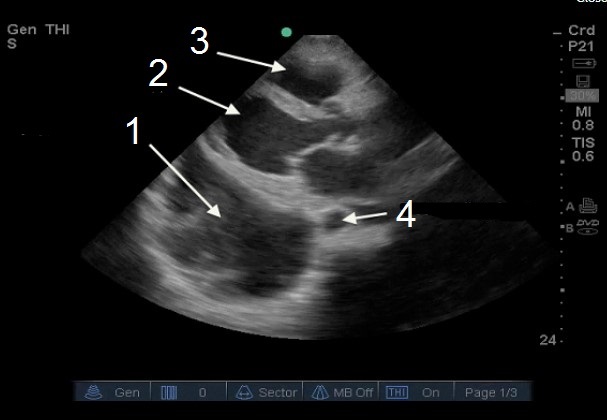

胸腔穿刺、心臓傍胸骨長軸(PLAX)胸水の画像

胸水(液体)

左心室(LV)

右心室 (RV)

下行大動脈